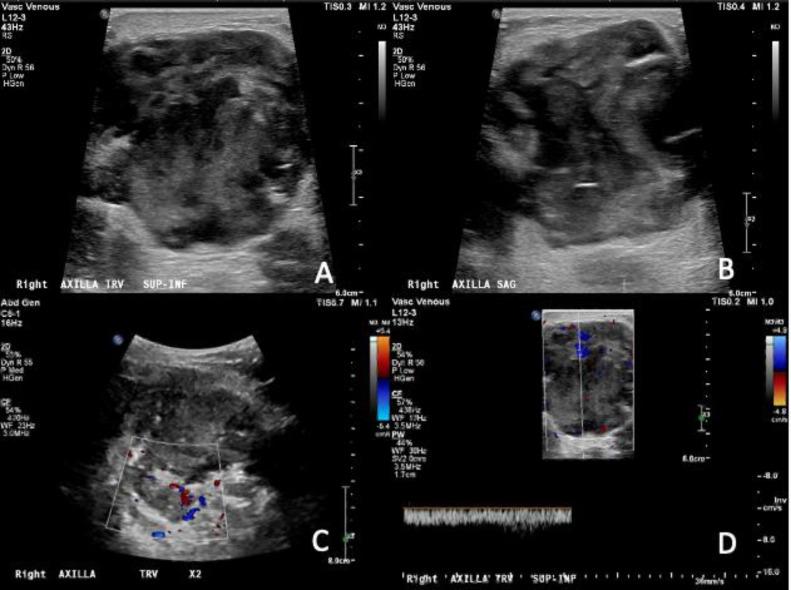

Metaplastic breast carcinoma is rare and may present as a highly aggressive subtype of breast cancer. In this case report of metastatic metaplastic breast carcinoma with osteosarcomatous differentiation in a female patient previously treated for invasive ductal carcinoma, we describe the new presentation of a palpable mass with associated calcifications on imaging near the site of prior partial mastectomy. This article will detail the clinical presentation, imaging findings, histopathology, and clinical course following treatment of our case. Knowledge of the clinical and imaging presentation of this rare subtype, which can present with benign features on mammography and ultrasound, can facilitate timely diagnosis as treatment paradigms evolve.

化生性乳腺癌较为罕见,可能是一种侵袭性很强的乳腺癌亚型。在本病例报告中,一名曾接受浸润性导管癌治疗的女性患者发生了具有骨肉瘤分化的转移性化生性乳腺癌,我们描述了在先前保乳手术部位附近出现可触及肿块并伴有影像学钙化的新表现。本文将详细介绍我们病例的临床表现、影像学检查结果、组织病理学以及治疗后的临床病程。随着治疗模式的发展,了解这种罕见亚型在乳腺X线摄影和超声检查中可能表现出良性特征的临床和影像学表现,有助于及时诊断。